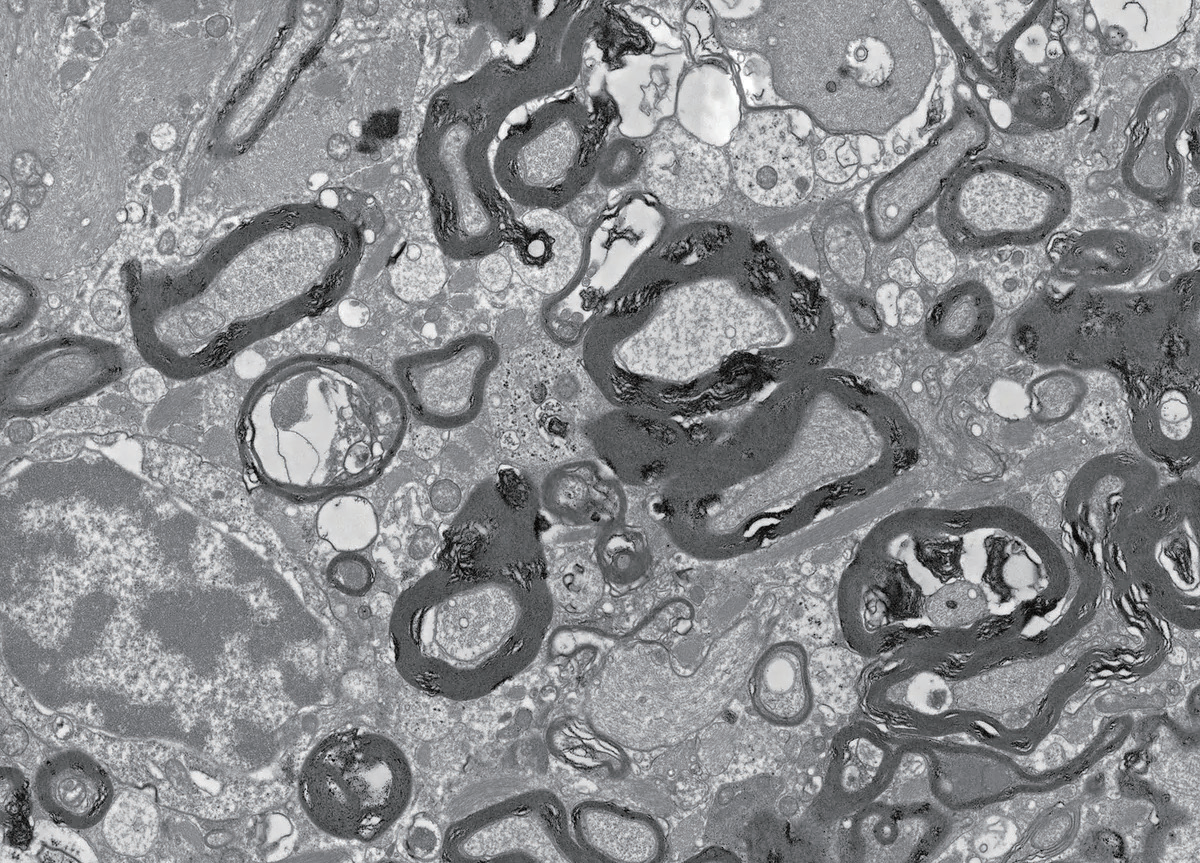

电子显微镜显示,ALSP患者脑白质中轴突周围的髓鞘过度生长。髓鞘失稳与最终退行性改变是神经退行性疾病的特征

实验证明FIRE小鼠髓鞘形成功能并没有缺陷。研究者很疑惑,并花费数月分析了各种髓鞘相关蛋白质的情况,同时研究了少数胶质细胞的数量,但它们似乎全都没有受到影响。最后,研究者利用电子显微镜在超微结构水平进行观察,并取得了突破性进展。研究者观察到FIRE小鼠确实存在髓鞘,但其数量却丰富得出人意料。年轻的FIRE小鼠脑中缺乏小胶质细胞,却在发育过程中形成了过量的髓鞘,并维持到了成年。

接着,研究者探究这一现象是否也出现在人类中。研究人员从柏林夏里特医学院维尔纳? · ?斯坦泽(Werner Stenzel)那里获得了一种罕见的人类神经退行性疾病——成人起病的脑白质病伴轴索球样变和色素胶质细胞(ALSP)——珍贵脑组织样本,发现ALSP患者CSF1R基因的杂合突变会导致小胶质细胞数量大约减少一半,尤其是脑白质中富含髓鞘的区域。ALSP患者临床上会表现出早发性痴呆,通常在40或50岁左右去世。ALSP患者的脑样本中也出现了FIRE小鼠脑中过度生长的髓鞘。